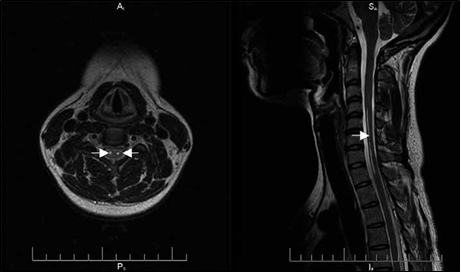

La IRM (imagen de resonancia magnética) de médula cérvico-dorsal mostró en sector anterior dos imágenes tubulares, hiperintensas en T2, hipointensas en T1, sin refuerzo con contraste (Fig. 2). Los estudios de conducción nerviosa y la electromiografía mostraron signos de compromiso axonal motor de nervio cubital y mediano en miembro superior derecho y signos denervatorios en territorio C6 y C7 bilateral. Se dosaron anticuerpos GM1 en sangre con resultado negativo.

Figura 2. Signo de ojos de serpiente (flechas

blancas).Hiperintensidad a nivel

del asta anterior en corte axial

(imagen izquierda) y sagital (imagen

derecha)

de la secuencia T2 de la imagen por

resonancia magnética de médula cervical que se extienden desde C3 a C7 y de D1 a D2.